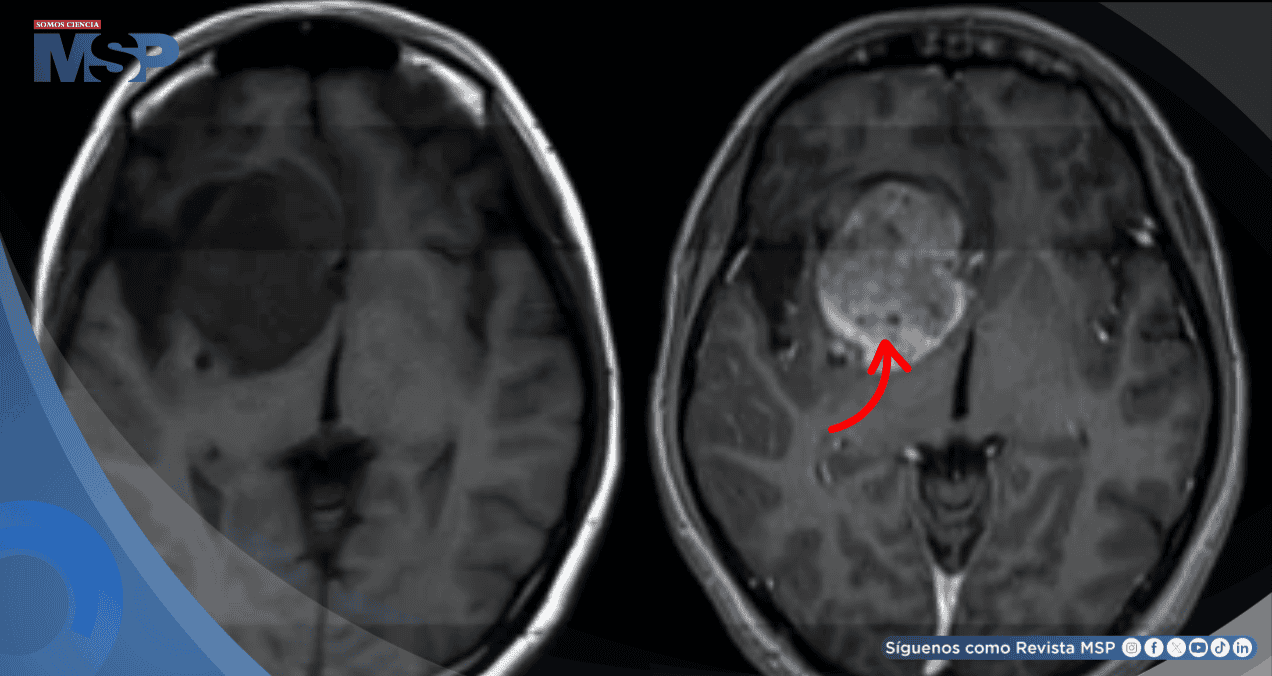

En los últimos años, el tratamiento de los gliomas, un tipo de tumor cerebral, ha experimentado una transformación radical gracias a la medicina de precisión. El descubrimiento clave fue la identificación de una mutación en el gen IDH (isocitrato deshidrogenasa), que distingue a un subgrupo de pacientes con pronóstico más favorable y abre la puerta a terapias específicas.

El cambio de manejo llegó con la aprobación por parte de la FDA en agosto de 2024 del vorasidenib, el primer inhibidor de IDH. Esta aprobación se basó en los resultados del ensayo clínico INDIGO, que incluyó a pacientes con astrocitomas u oligodendrogliomas de grado 2 con mutación IDH y enfermedad residual no realzada.

El ensayo demostró una "mejora significativa en la supervivencia libre de progresión de los pacientes que recibieron vorasidenib", un beneficio que se mantuvo independiente de otros factores clínicos.